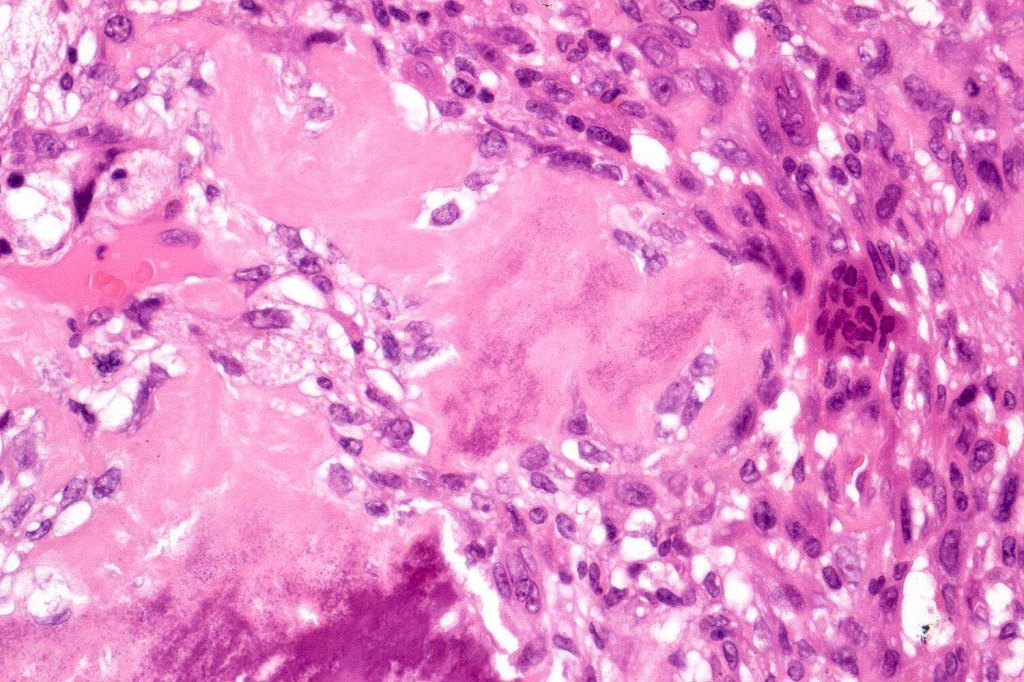

Carcinosarcoma

Cutaneous carcinosarcoma (metaplastic carcinoma, carcinoma with heterologous differentiation)

Histological features

•Osteoid

•Chondroid

•Smooth muscle

•MFH-like features with osteoclasts

•Neural differentiation